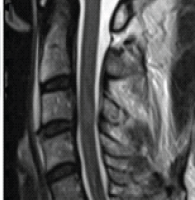

A 29-year-old male was brought to the emergency department following accidental impalement of the left forearm by an iron rod (Fig. 1). The injury occurred while the patient was under the influence of alcohol and involved a fall over a metal gate in the Ambarnath industrial area. The rod was approximately 1 inch in diameter and had entered the volar forearm and exited dorsally near the base of the thumb. The rod was cut at the scene with an angle grinder by rescue personnel, and the patient was transported to our center.

Figure 1: Initial presentation of upper limb impalement injury. Clinical photograph showing the iron rod traversing the left forearm with the volar entry wound and dorsal exit near the base of the thumb. Plain radiograph confirming the trans-forearm trajectory of the foreign body without bony involvement.